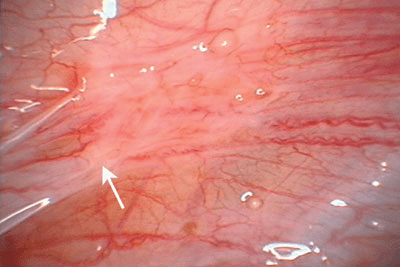

Figure 3 : Une endométriose discrète chez une adolescente peut être pratiquement incolore. Il est possible d’observer sur le ligament large gauche des papules claires et des macules blanchâtres, chacune avec une glande endométriosique (flèche) visible sous la surface péritonéale.